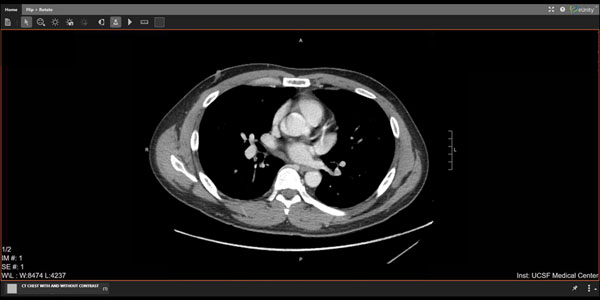

This month, UCSF Medical Center announced that patients can now see radiographic studies including X-rays, MRIs, CT scans and some ultrasounds on MyChart. Such a move is an additional step towards transparency and will allow patients to read reports and see images. We are the 19th Epic customer in the U.S. to use MyChart to make images available to patients, the second in California and the first University of California hospital.